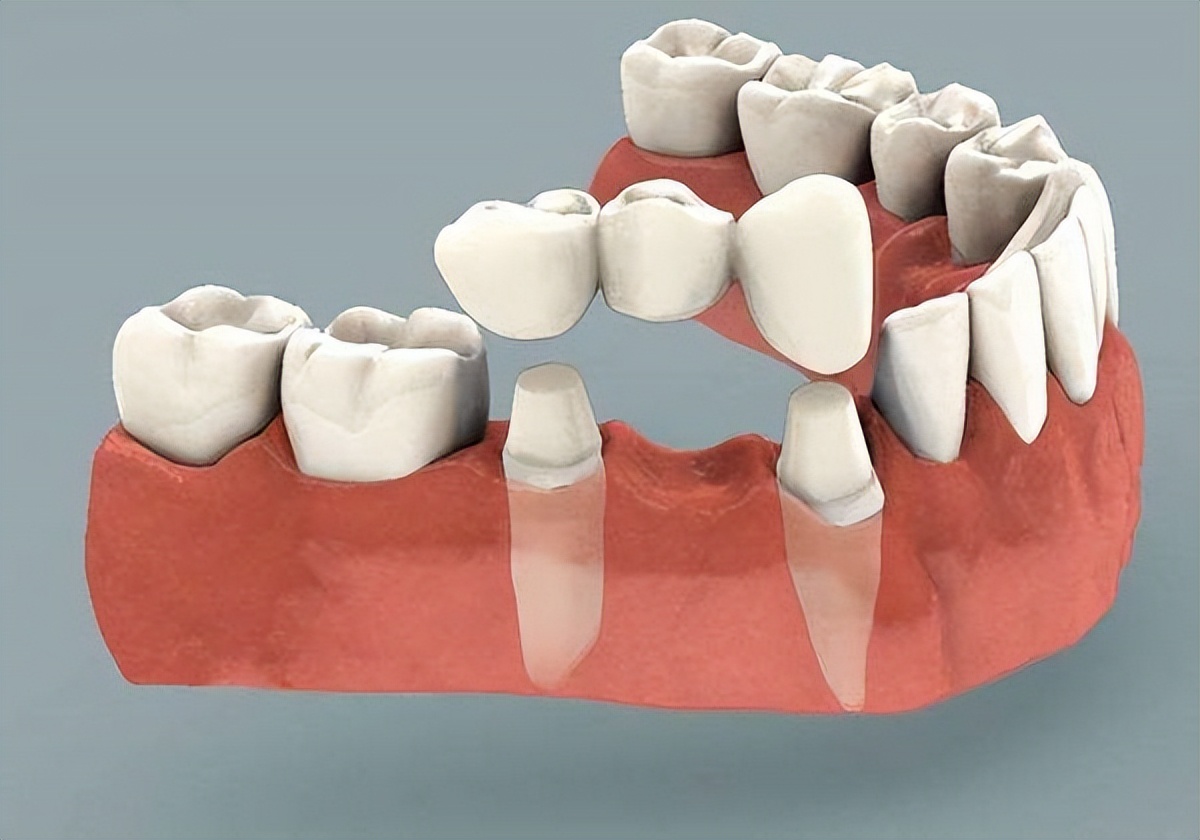

2、使用桥体牙冠修复

桥体牙冠修复也不具有单独的牙根,需要依靠邻牙进行支撑,相比较活动假牙要更为稳固,对于缺牙处牙龈的施压也相对较小。因此对于预防牙槽骨吸收、丧失具有不错的作用。